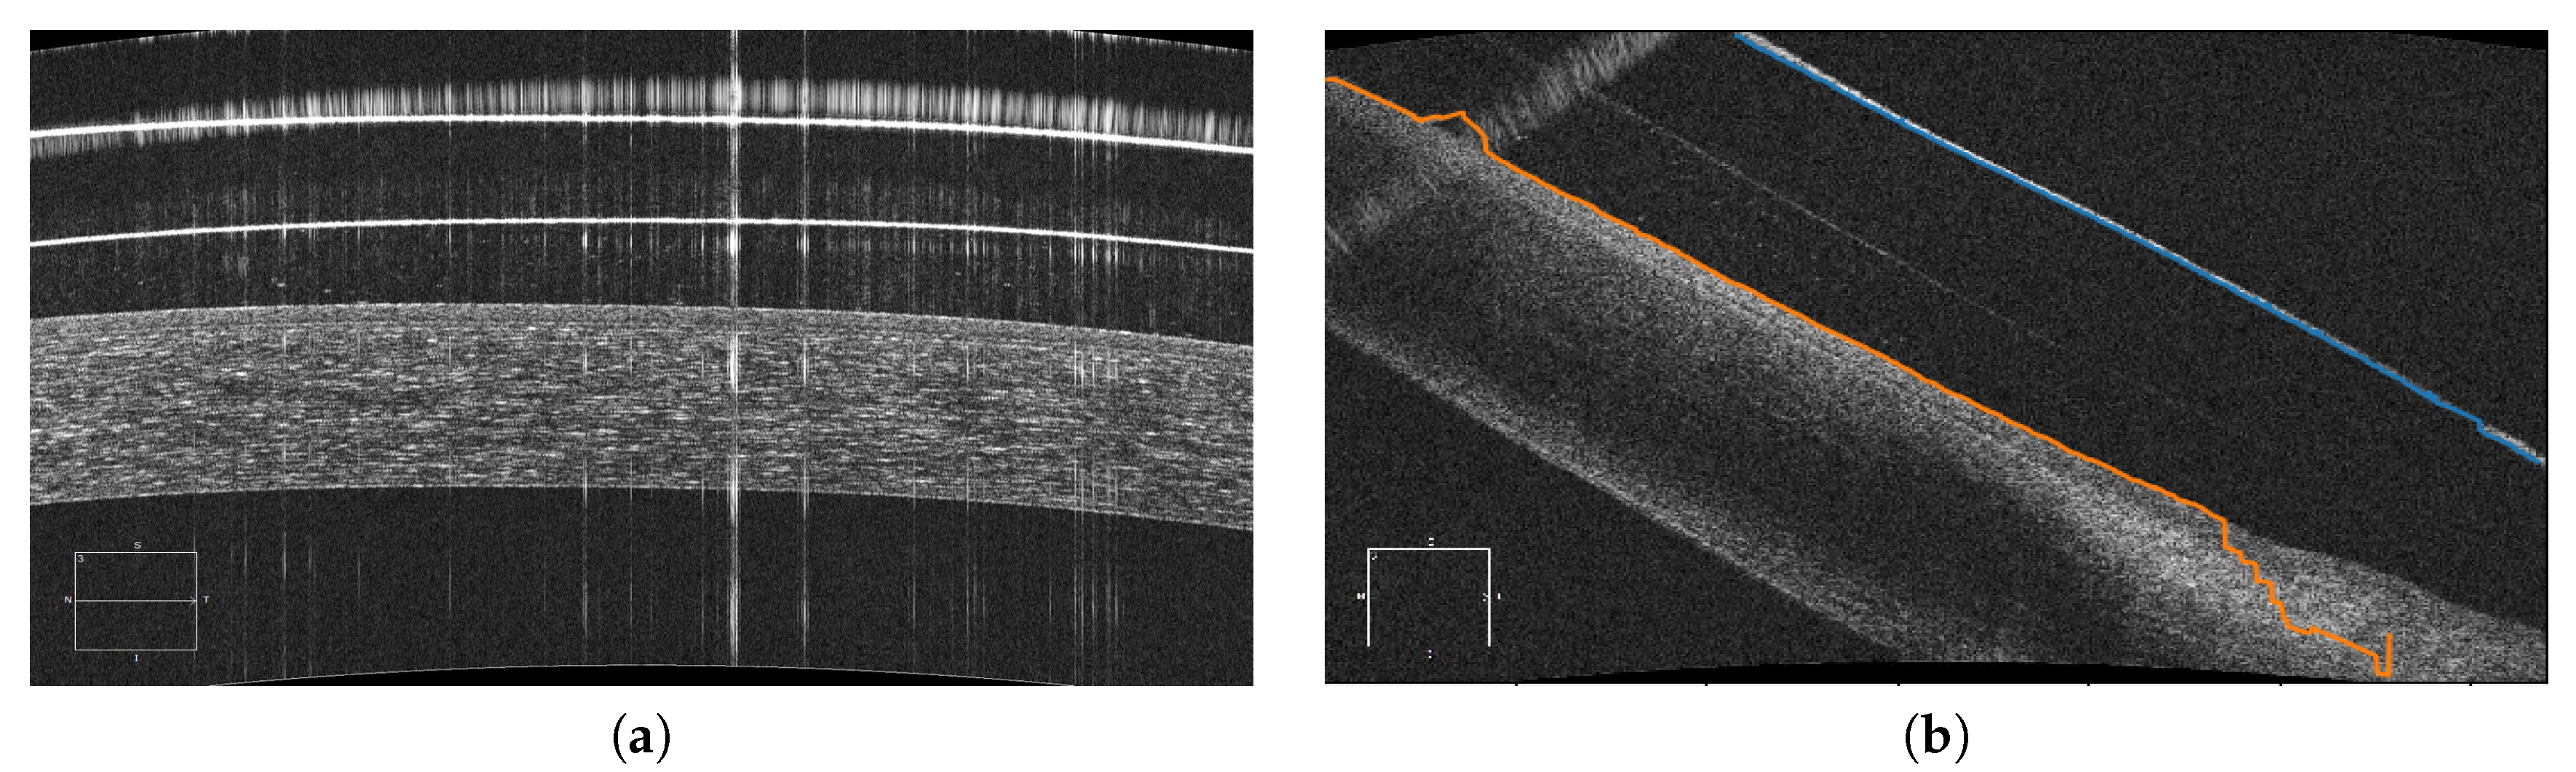

For this purpose, new diagnostic imaging techniques are currently increasing in relevance, among which anterior segment optical coherence tomography (AS-OCT) images stands out. AS-OCT was developed in 1994 by Izatt et al. [3] and is today one of the most informative modalities used in the study of the anterior chamber or segment, the area in the anterior third of the eye from the back surface of the cornea to the crystalline lens. Its use does not require any contact, being non-invasive for the patient and producing images of both the anterior and posterior segments. These images allow the study of both the thickness and volume of the entire cornea as well as the biometry of the camera, having applications in contact lens (CL) fitting, diagnosis and clinical evaluation, surgical planning and monitoring of patients with many significative eye diseases [4]. Moreover, they allow the detection of micro-structural changes in the cornea of the patient, being very useful for studying the characteristics of the relationship between the CL and the cornea. However, the lack of automatic procedures requires manual study by the clinical experts, making the process extremely difficult and limiting the amount of information that is extracted from the images. Figure 1 shows representative examples of AS-OCT images that were obtained from different eye regions.

While there exist different works in the literature about the analysis of AS-OCT images, to date there is no other methodology designed for the study of the relationship between the cornea and the SCL, as in our case. This work proposes a fully automated system for the extraction of the region of the SCL and the cornea using AS-OCT images in the analysis of the entire eye region. In particular, the study is performed not only in the typical central region but also in the most complex cases as the lateral and the extreme regions of the eye represent. Figure 1 presents representative examples of the three possible regions of analysis (central, lateral and extreme) as well as their corresponding general locations in the eye. This comprehensive approach implies a complex analysis with zones that present a significant variability in contrast and orientation. Then, using the obtained cornea and SCL segmentations, we calculate representative distance metrics that quantify their relationship. Specifically, we obtain three metrics: The vertical distance between the SCL and the cornea, the normal distance to the tangent of the points of both the SCL and the cornea and the closest distance point of the points of both the SCL and the cornea. These different metrics can be used to study the comfort or potential damage that the CL can produce in the eye, selecting the different curves of SCL to maintain a correct vault throughout the cornea. With this, we aim at demonstrating the usefulness of the automatic analysis of the cornea–CL relationship in AS-OCT images by obtaining complex metrics that are not feasible to measure by manual analysis. Additionally, the method builds and returns a clear and intuitive colored visualization system that facilitates the posterior analysis and diagnosis of the expert clinicians.

The proposed methodology receives as input one or more AS-OCT image with the information of the biological tissues corresponding to the cornea and the SCL. Typically, these images correspond to the central cornea (Figure 1d) where the SCL always maintains a distance to the cornea, the peripheral cornea and the limbus (Figure 1c,e) where the inner layers of the SCL progressively approach and finally join the sclera or the region of the extreme of the SCL (Figure 1b,f) where the outer layer is the one that meets the sclera.

Figure 1. Schematic representation of anterior segment optical coherence tomography (AS-OCT) images. (a) An illustrative example of the anterior pole segment, including sclera, limbus, central cornea, peripheral cornea and scleral contact lens. (b,f) Extreme regions of the SCL where the outer layer is the one that meets the sclera. (c,e) Peripheral cornea and limbus region where the inner layers of the SCL progressively approach and finally join to the sclera. (d) Central cornea where the SCL always maintains a distance to the cornea.